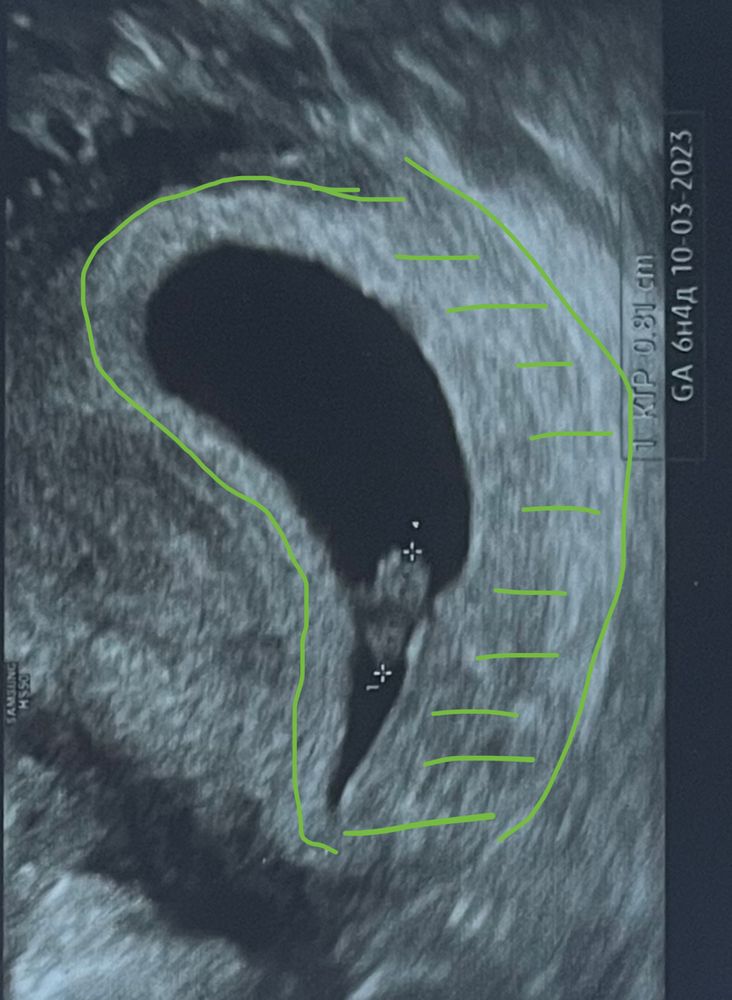

6 недель, отзеркалила.

Так было в оригинале по животу

Подскажите, кто наша креветочка?